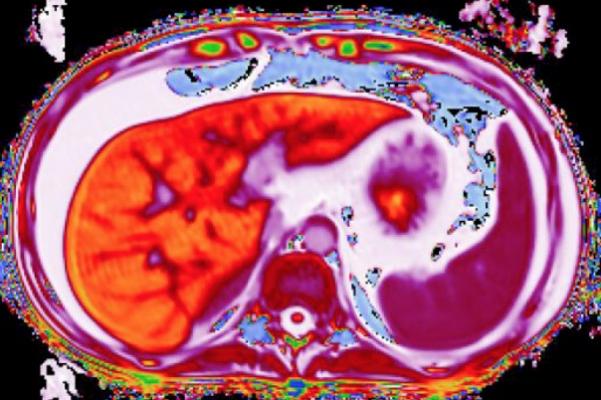

Used in the clinical management of patients with chronic liver disease, LiverMultiScan is the only imaging test cleared to detect early-stage liver disease. The technology offers a quantitative liver assessment in a safe, non-invasive, 15-minute MRI scan. Analysis is based on assessment of native properties of liver tissue, accurate measurement of liver fat and other metrics without the need for additional diagnostic technologies or contrast agents.

LiverMultiScan utilizes quantitative MR methods, similar to recent developments in cancer and cardiac imaging, and has been shown to predict clinical outcomes for patients with liver disease. This technology provides a highly detailed map of the whole liver, making it possible to precisely identify regions of disease. This scalable technology enables as many as six patients to be tested in an hour using one MR system, with a 95-97 percent success rate. The technology can help reduce patient turnaround time and the need for retesting associated with other methods.